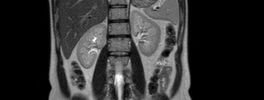

Kidney MRI